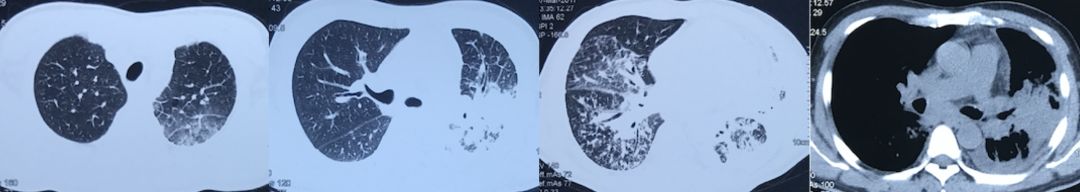

胸部影像学

2016-12治疗前:

2017-3抗生素治疗后:

2017-5激素治疗后:

? 中年男性,慢性病程,近期加重? 咳嗽、咳痰、气短,发热、盗汗、体重下降,利奈唑胺+头孢哌酮舒巴坦对发热似乎有效? 颈部稍增大淋巴结,肺部湿罗音? 血白细胞、中性粒细胞显著升高,炎症指标明显升高,LDH升高? 胸部CT:双肺病变,左肺大片斑片渗出影,后表现为空洞,病程中右肺出现小叶间隔增厚,沿支气管血管束斑片、结节影,纵隔淋巴结肿大,左侧胸腔积液。